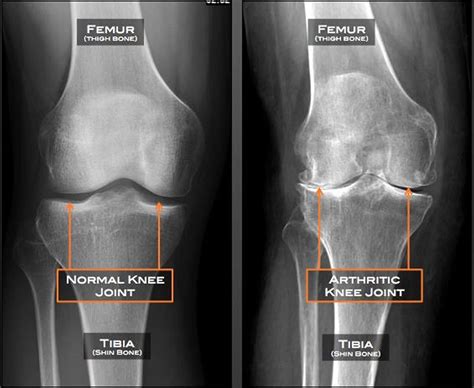

Tricompartmental degenerative arthrosis, often referred to as osteoarthritis, is a progressive condition that affects the joints, causing significant pain and disability. This condition is characterized by the degeneration of the cartilage that cushions the ends of the bones within the joint. Understanding the causes, symptoms, and treatment options for tricompartmental degenerative arthrosis is crucial for managing this debilitating condition effectively.

Tricompartmental degenerative arthrosis specifically affects the knee joint, which is divided into three compartments: the medial (inner), lateral (outer), and patellofemoral (front) compartments. When all three compartments are affected, it is termed tricompartmental. This condition is more common in older adults but can also occur in younger individuals due to injury or genetic predisposition.

Diagnosis of Tricompartmental Degenerative Arthrosis

• Imaging Tests: X-rays, MRI, or CT scans may be ordered to visualize the joint and assess the extent of cartilage damage.